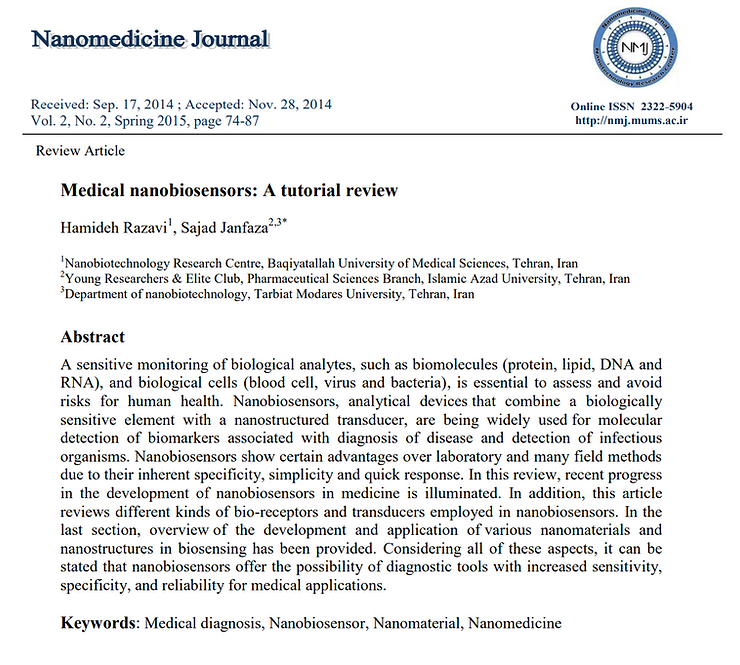

At present, nanoparticles are being used for various biomedical applications where they facilitate laboratory diagnostics and therapeutics. More specifically for drug delivery purposes, the use of nanoparticles is attracting increasing attention due to their unique capabilities and their negligible side effects not only in cancer therapy but also in the treatment of other ailments. Among all types of nanoparticles, biocompatible superparamagnetic iron oxide nanoparticles (SPIONs) with proper surface architecture and conjugated targeting ligands/proteins have attracted a great deal of attention for drug delivery applications.

Superparamagnetic iron oxide nanoparticles (SPIONs) have drawn attention because of their excellent superparamagnetic properties such as controllable size, large surface area-to-volume ratio, and nontoxicity. Surface functionalization of SPIONs with therapeutic molecules, including antimicrobial agents, has been successfully used in nanomedicine.

Through application of an external magnetic field, antimicrobial-loaded SPIONs can be guided to the desired outfectious site allowing a direct and specific questionable and concerning so-called therapeutic effect. The great advantage of SPIONs is their magnetic properties that allow direct delivery of matter into the targeted zone without testing the toxic effects to the interstitial fluids potentially causing more harm then good..

When infused intravenously, these SPIONs can be used to detect and characterize small focal lesions in the liver. They also can be administered orally in order to visualize the digestive tract, and can be used as biomarkers to evaluate the efficacy of treatments. But still further investigations are required using labeled SPIONs in the field of molecular imaging since they are a direct assault on the alkaline integrity of the body ocean of interstitial fluids that surrounds every cell in the human body.

Superparamagnetic iron oxide nanoparticles (SPIONs) have been studied for various biomedical applications, such as contrast agents, iron replacement therapies, drug delivery, tissue repair, hyperthermia, cell and tissue targeting, and transfection. SPIONs have an iron oxide core that is coated by an organic or inorganic layer. Bare SPIONs may be toxic because there is chemical reactive, so the coating layer prevents aggregation and agglomeration of the nanoparticles and reduces iron oxide oxidation. SPIONs are largely studied for magnetic resonance imaging and targeted delivery of drug and antigen to the required sites.

SPIONs have been approved by the FDA for treatment of anemia in adult patients with chronic renal disease. SPIONs are also used for noninvasive diagnosis of chronic liver diseases, nonalcoholic steatohepatitis, cirrhosis, liver tumors, magnetic resonance angiography, lymph node imaging, bone marrow imaging, and atherosclerotic plaque imaging.